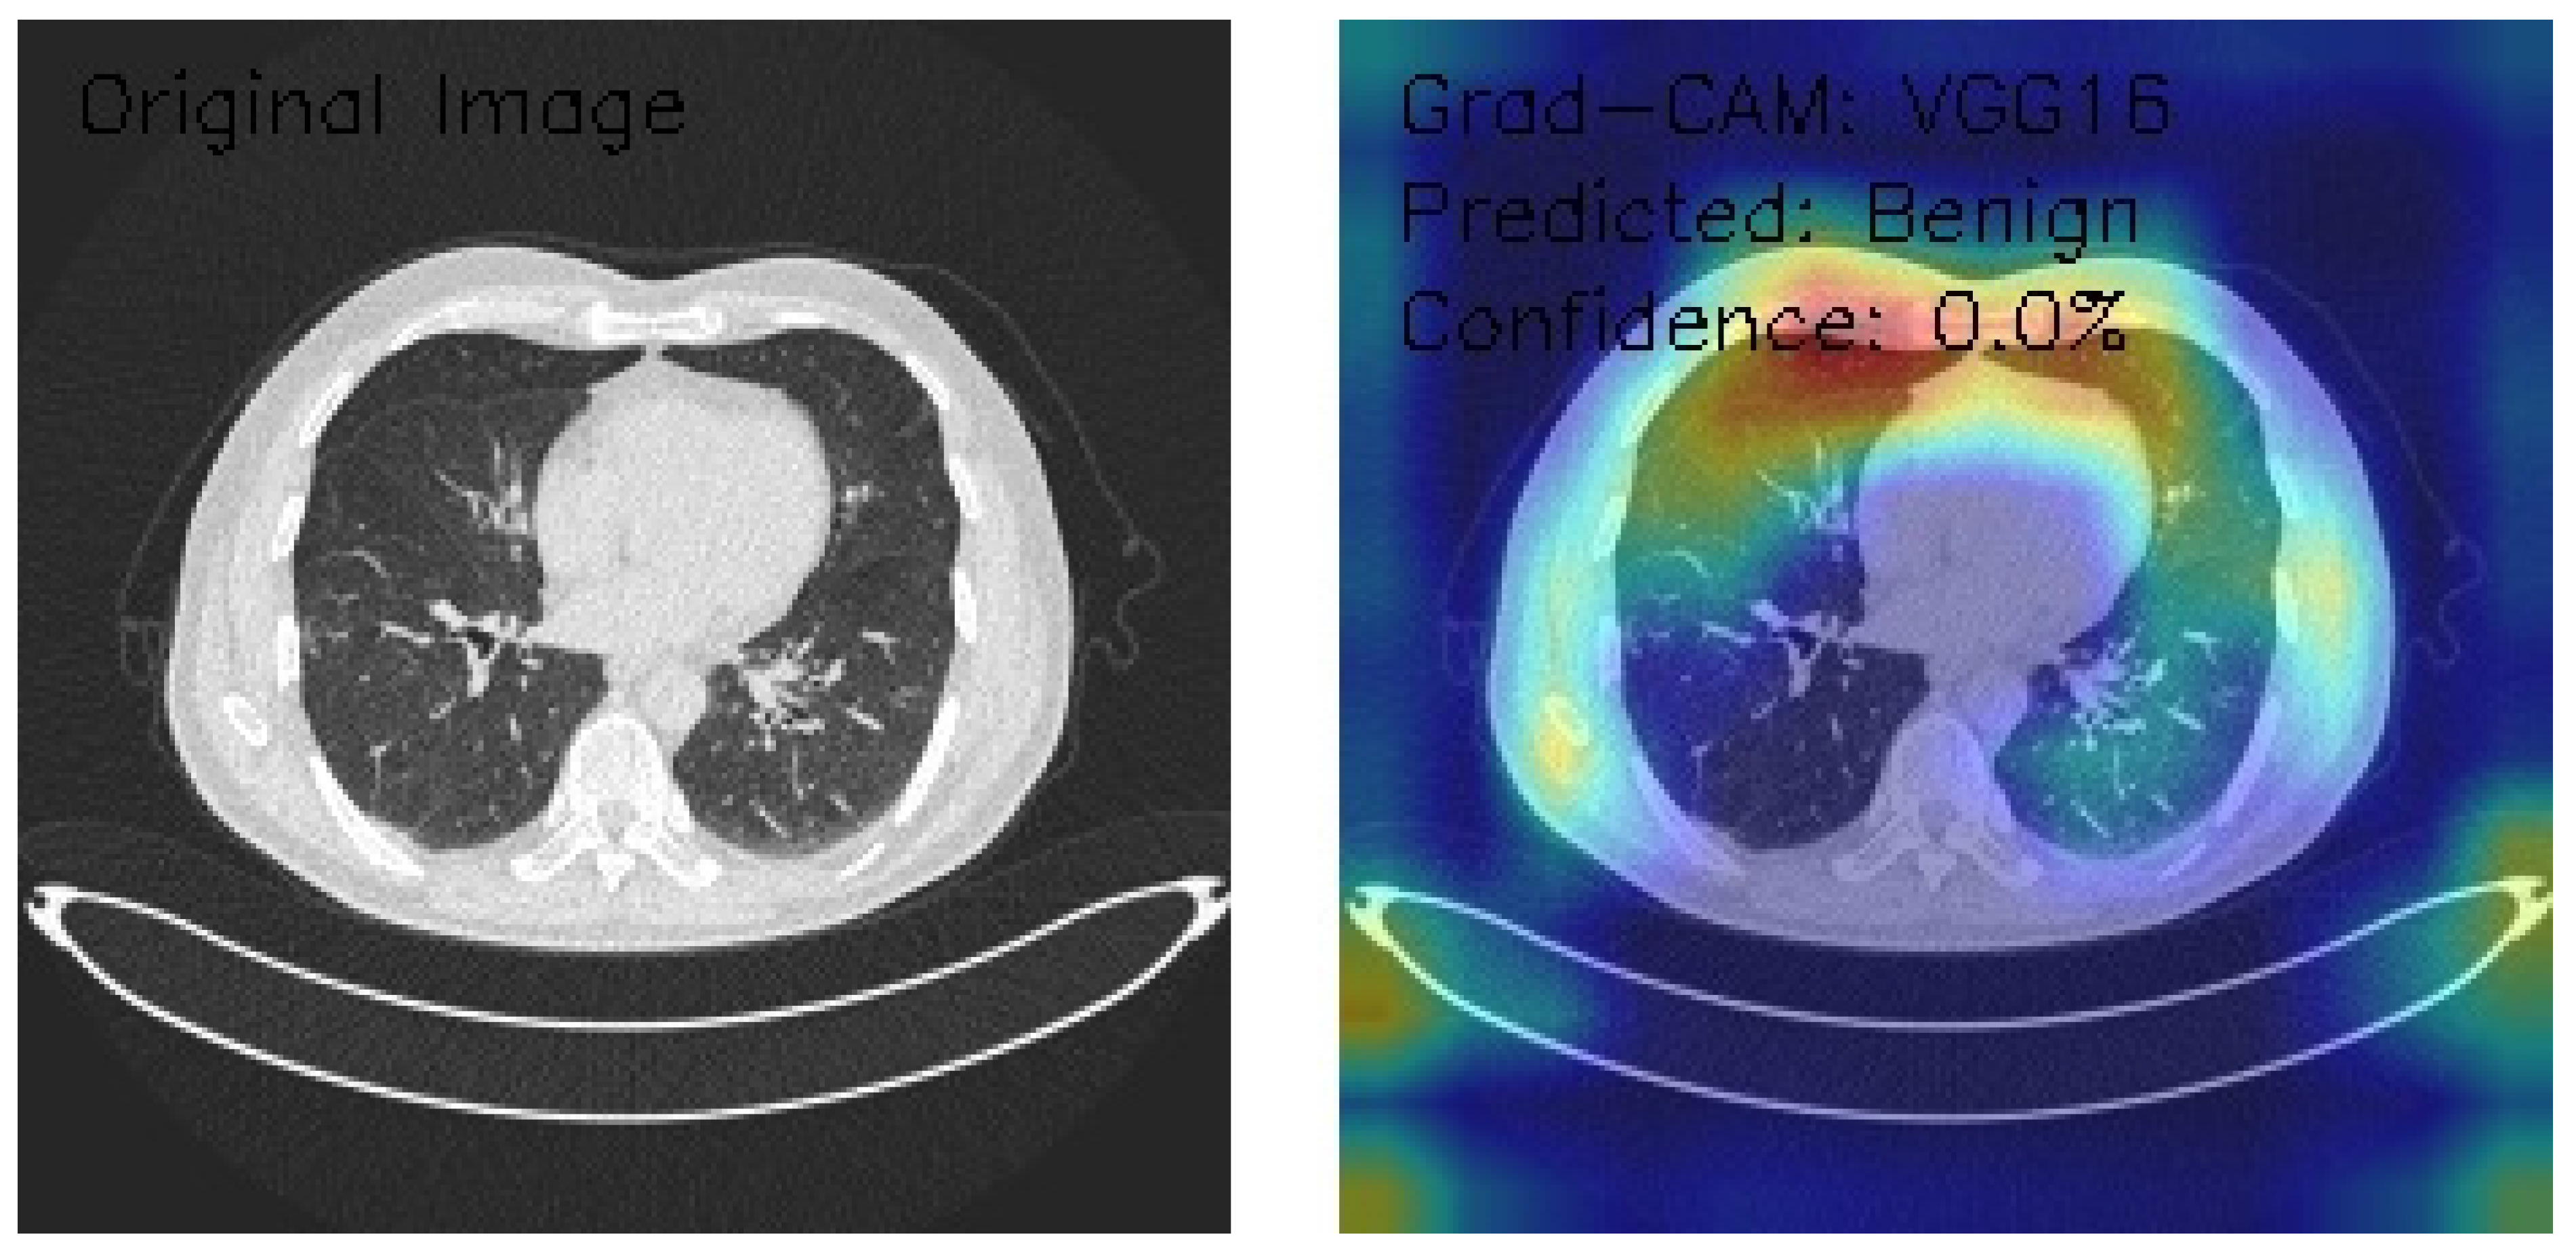

VGG16 Model Analysis of Lung CT Images with Grad-CAM Visualization

The results section of this analysis provides a detailed examination of three axial chest CT images analyzed through the VGG16 architecture, a widely recognized convolutional neural network model. We employed Grad-CAM, an advanced visualization technique, to gain insights into the model’s decision-making processes and focus areas. This method highlights the regions of the input images the model considers most significant when making predictions, offering a comprehensive view of its attention patterns. By integrating Grad-CAM with the VGG16 framework, this analysis illustrates the model’s effectiveness in interpreting medical imaging data and provides a transparent mechanism to evaluate its decision rationale. The findings presented aim to shed light on the nuanced interactions between the neural network and the image features, contributing to the broader understanding of AI-assisted diagnostic methodologies.

Figure 16 shows the CT image demonstrating interstitial patterns with branching structures, and the Grad-CAM visualizations indicate bilateral peripheral activation, with strong emphasis along the lateral chest wall interfaces. The model classifies the image as Benign with a confidence score of 0.0%, reflecting significant uncertainty in its decision-making process despite the clear focus on relevant anatomical regions. The bilateral peripheral activation pattern suggests that the model effectively identifies features of interest, but the low confidence highlights a disconnect in translating these observations into reliable classifications. Enhancing the model’s calibration and optimizing its classification layers are crucial to improving its clinical utility.

Figure 16.

Figure 17 shows the CT image depicting clear lung fields, with Grad-CAM visualization showing focal activation in the right upper lung and notable attention to the hilar regions. The activation pattern demonstrates a right-sided predominance, suggesting the model’s sensitivity to specific anatomical features. Despite these observations, the model classifies the image as Benign with a confidence score of 0.0%, indicating significant uncertainty. This mismatch between detected features and classification confidence suggests the need for model recalibration, improved classification layer optimization, and enhanced confidence scoring mechanisms to ensure reliable and actionable diagnostic outcomes.

Figure 17.

The VGG16 model, applied to three chest CT images with Grad-CAM visualizations, demonstrates strong capabilities in localizing anatomical features but struggles with reliable classification due to uniformly low confidence scores. Image A, showing scattered nodular opacities, reveals intense bilateral upper lung activation with a predominant right-sided focus, yet is classified as Normal with 0.0% confidence. Image B highlights peripheral lung field activation and lateral chest wall emphasis in the presence of interstitial patterns, classified as Benign with 0.0% confidence. Image C, featuring clear lung fields, displays focal activation in the right upper lung and hilar regions, but is similarly classified as Benign with 0.0% confidence. While the model excels in highlighting regions of interest with precise and consistent attention patterns, its limited confidence and conservative classification behavior highlight the need for calibration and optimization. These findings suggest potential utility in feature detection and initial screenings, provided enhancements to confidence scoring and classification thresholds are implemented.